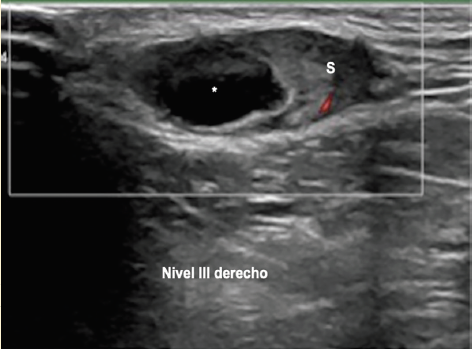

Además, la masa palpable se localiza en el nivel ganglionar III derecho, la cual se visualiza como un ganglio linfático de 27 mm con morfología globular, con componente quístico y sólido, pérdida del hilio ecogénico y flujo periférico (figura 4), en el nivel III izquierdo se identificaron otros 2 ganglios con morfología ovoide, componente mixto y ecos puntiformes en su interior.

Figura 4 Ganglio linfático de 27 mm en el nivel III derecho con una parte quística (*) y otra sólida (S), además de pérdida del hilio graso normal, hallazgos que sugieren etiología maligna.